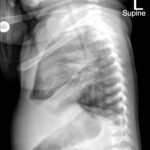

Infant tuberculosis (TB) is a rare but potentially deadly infection and difficult to diagnose, especially in infants who may present with non-specific symptoms. Here, we report a case of an United States-born term infant with community-acquired miliary TB and no confirmed TB exposure history. The patient initially presented with respiratory distress at seven weeks of life with chest radiograph showing a right lower lobe (RLL) infiltrate. After failing multiple courses of treatment for community-acquired pneumonia and developing growth faltering, the patient had imaging findings suggestive of TB infection with CNS involvement. The diagnosis of TB was confirmed by QuantiFERON and purified protein derivative (PPD). In infants who fail conventional treatment for bacterial pneumonia, the differential should be broadened to consider alternative etiologies. Additionally, brain imaging should be performed in cases of disseminated TB despite negative cerebrospinal fluid (CSF) studies since these patients are at high risk of central nervous system (CNS) involvement.